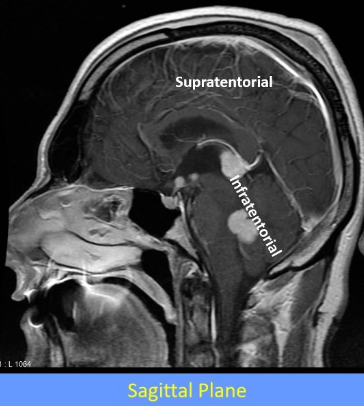

What is the tentorium cerebelli and what does it do

tent shaped fold of dura mater

divides the intracranial cavity into supratentorial and infratentorial compartments

What divides the supratentorial compartment

divided by the falx cerebri into the left and right supratentorial space which can communicate with each other and with the infratentorial space

Label this image